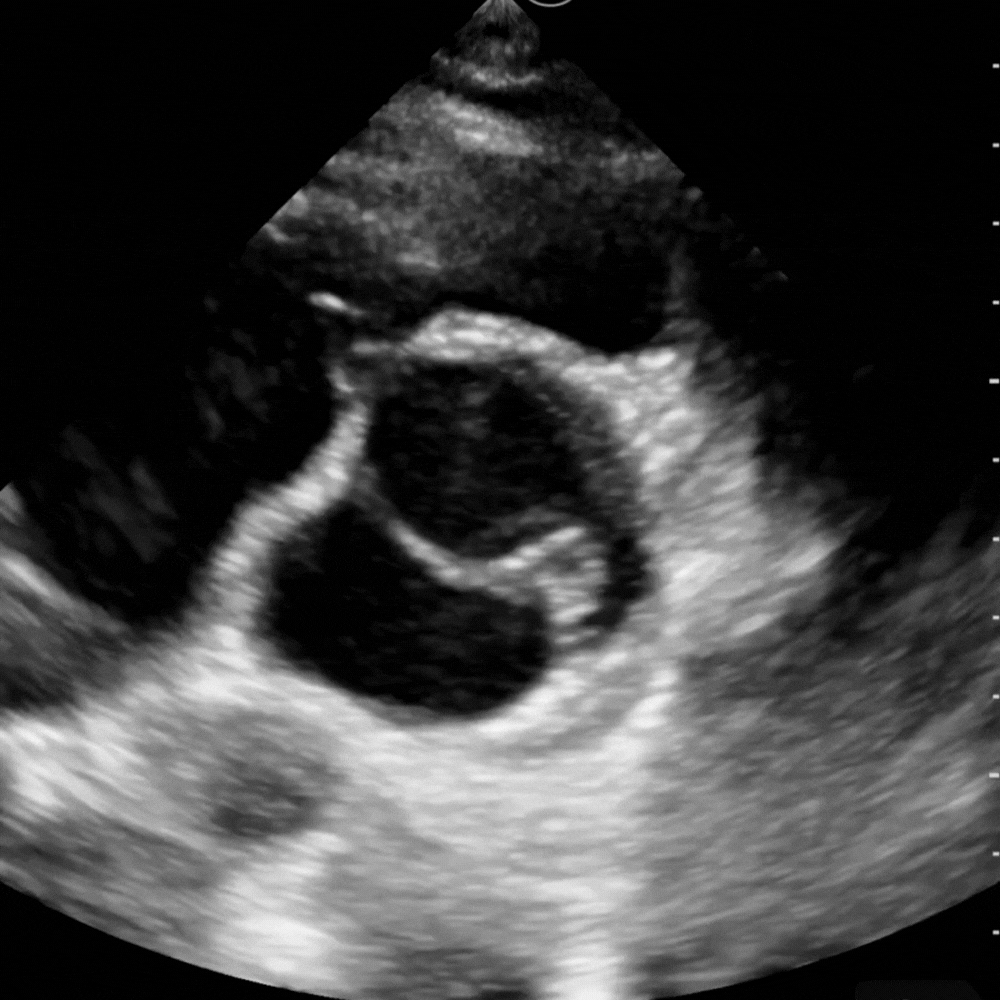

🔹 Vue Sous-costale (subxiphoïdienne)

→ Le cœur bouge-t-il ? y a-t-il du liquide ?

Placer la sonde sous l’appendice xiphoïde, dirigée vers l’épaule gauche, en s’aidant du foie comme amplificateur acoustique.

C’est la fenêtre universelle de la réanimation, utilisable pendant la RCP.

Elle permet de visualiser les quatre cavités, de détecter un épanchement péricardique même discret, et d’apprécier grossièrement la fonction myocardique.

Un simple regard suffit à trancher entre activité cardiaque présente ou asystolie réelle.